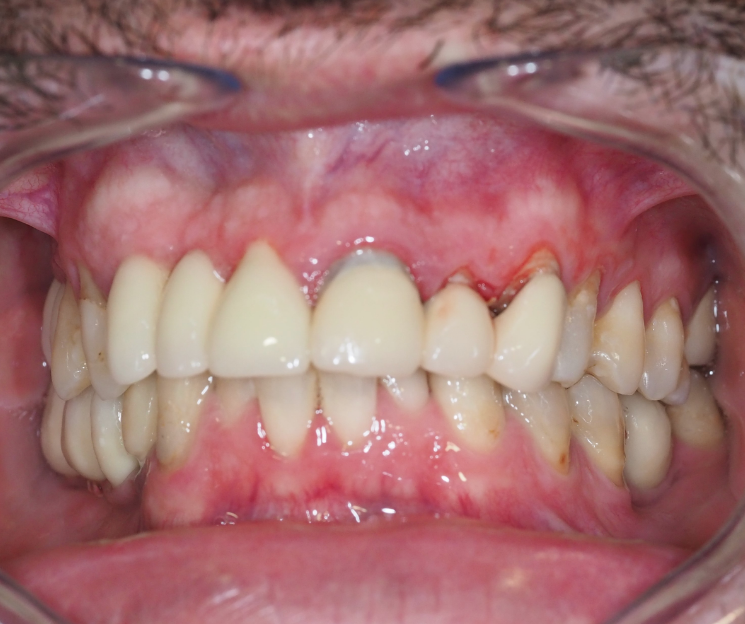

Paciente con infecciones de origen dental que comprometían severamente el hueso alveolar en la zona anterior superior. Se realizó la extracción de los dientes 21, 22 y 23, y se optó por una rehabilitación inmediata mediante implantes córticobasales.

Esta combinación permitió anclar los implantes en hueso cortical, que mantiene su estabilidad incluso en presencia de procesos infecciosos en el hueso alveolar. El resultado: rehabilitación funcional y estética el mismo día de la cirugía.

La rehabilitación postextracción de los dientes 21, 22 y 23 con implantes córticobasales no es un caso aislado. Es un ejemplo claro de cómo la odontología moderna puede resolver situaciones complejas de forma inmediata, estética y funcional.